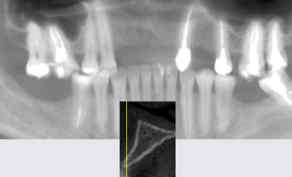

Computed tomography showed the presence of 3mm of remaining bone thickness, with medullary bone, and preservation of alveolar bone height (Figure 3). In view of the observed condition, the proposed planning was to carry out the Split Crest technique, installing 4 implants, replacing the 4 missing teeth.

Figure 3: Computed tomography showed the presence of 3mm of remaining bone thickness, with

medullary bone, and preservation of alveolar bone height.